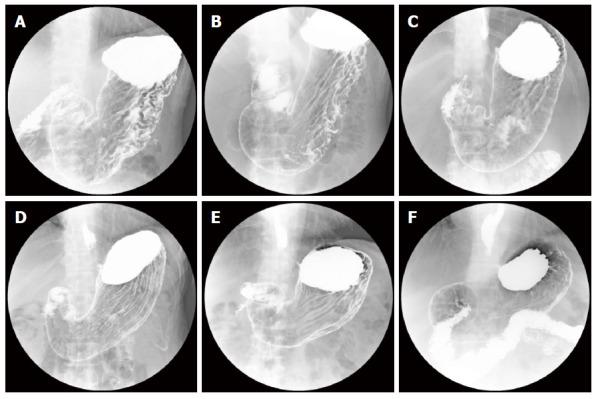

Preliminary study of automatic gastric cancer risk classification from photofluorography.

We used data for 2100 subjects including X-ray images, pepsinogen I and II levels, PGI/PGII ratio, () antibody, eradication history and interview sheets. We performed two-stage classification with our system. In the first stage, infection status classification was performed, and -infected subjects were automatically detected. In the second stage, we performed atrophic level classification to validate the effectiveness of our system.

Sensitivity, specificity and Youden index (YI) of infection status classification were 0.884, 0.895 and 0.779, respectively, in the first stage. In the second stage, sensitivity, specificity and YI of atrophic level classification for -infected subjects were 0.777, 0.824 and 0.601, respectively.